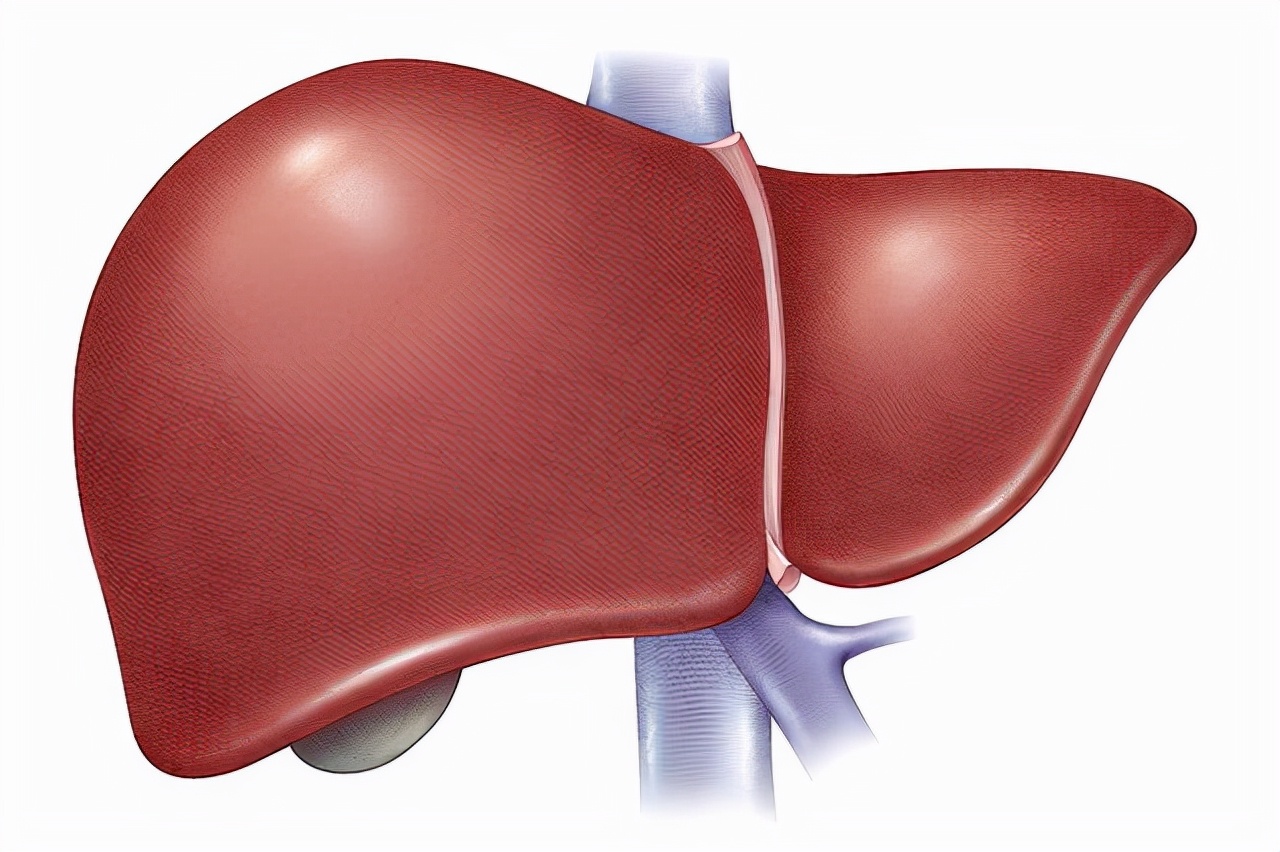

的右上腹部,是人体最大的实质性器官,由肝实质和一系列管道的间质组成

肝的外形解剖图-人体解剖图

肝脏